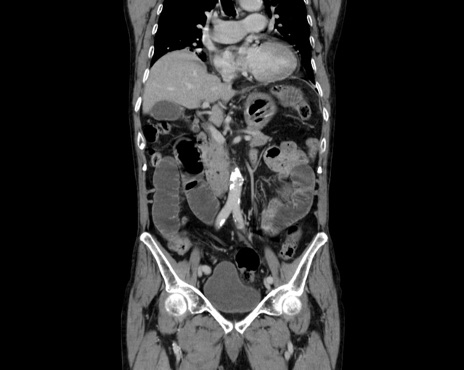

症例26(冠状断像)

【症例】80歳代男性

【主訴】嘔吐

【現病歴】昨晩2回嘔吐あり、今朝になっても嘔吐あり。来院。

【既往歴】胃潰瘍

【身体所見】意識清明、BT 37.6℃、BP 166/95mmHg、HR 100bpm、SpO2 97%、腹部:平坦・軟、腸蠕動音聴取良好、圧痛なし。

【データ】WBC 21900、CRP 1.4